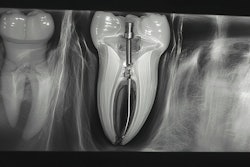

According to EDS, "BioSeal is an advanced endodontic sealer designed to promote extensive remineralization through its unique Directed-Formation Technology. By integrating calcium silicate, calcium phosphate, bioactive glass, chlorhexidine, and biomimetic polymers, BioSeal actively restores mineral content and strengthens treated teeth. This innovative formulation not only reinforces dental structures but also delivers continuous protection. BioSeal is compatible with both room temperature and warm vertical techniques."